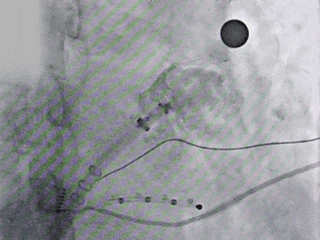

封堵器锚定位置良好

牵拉封堵器

封堵器稳定锚定

造影

Lefort封堵器评估符合PASS原则,释放封堵器,封堵器位置稳定且未见残余漏

术前结合CT以及术中造影评估左心耳开口23.27mm,深度22.45mm,心耳内部空间较大,且患者全身情况良好,可较配合局部麻醉手术,采用极简式封堵术安全可行。术中考虑心耳开口和深度充足,可利用心耳空间进行退鞘释放封堵器,使封堵器完全封堵左心耳。术中采用半回收方式调整封堵器在心耳内的位置形态,确保封堵器放置位置合适,且牵拉稳固,术后封堵器形态完整,未见残余漏。本病例展开后即刻造影,平口封堵,上下缘不留残腔。封堵器压缩比为10%,压缩合适,术中符合PASS原则,释放封堵器,术后封堵器稳固锚定在心耳壁,封堵器与心耳紧密贴合,无过度扩张风险,显著提升封堵完整性。